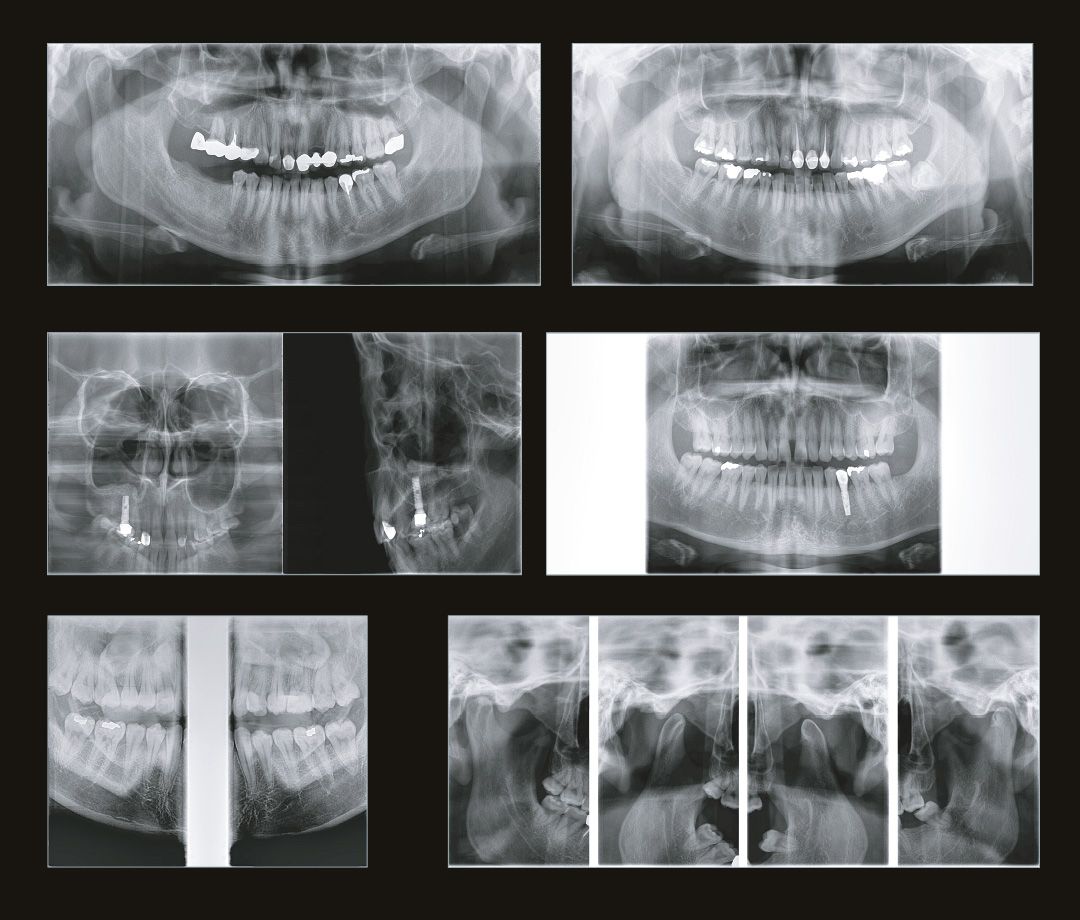

Но нормы размещения дентальных томографов всё же существуют. И, чтобы установить такой аппарат в вашей стоматологической клинике, вам необходимо получить несколько документов, а именно:

• санитарно-эпидемиологическое заключение на право эксплуатации медицинского рентгеновского аппарата;

• лицензию на медицинскую деятельность по специальности «Рентгенология»;

• лицензию на право деятельности в области использования источников ионизирующего излучения (данная лицензия отменена с ноября 2011 г. согласно Федеральному закону «О лицензировании отдельных видов деятельности» № 99-ФЗ от 04.05.2011 г.).

Если же ваша стоматологическая клиника располагается в жилом доме, помимо всего написанного выше, необходимо, чтобы дентальный томограф имел мощность излучения не выше 70кВ. Современные изготовители позаботились и об этом. На рынке представлено несколько моделей, которые удовлетворяют этим требованиям. Например, модель дентального томографа Papaya 3D (Plus) от компании Genoray имеет мощность излучателя 60~69 кВ и может располагаться в жилых помещениях, не принося вред жильцам и удовлетворяя санитарно-эпидемиологическим требованиям.